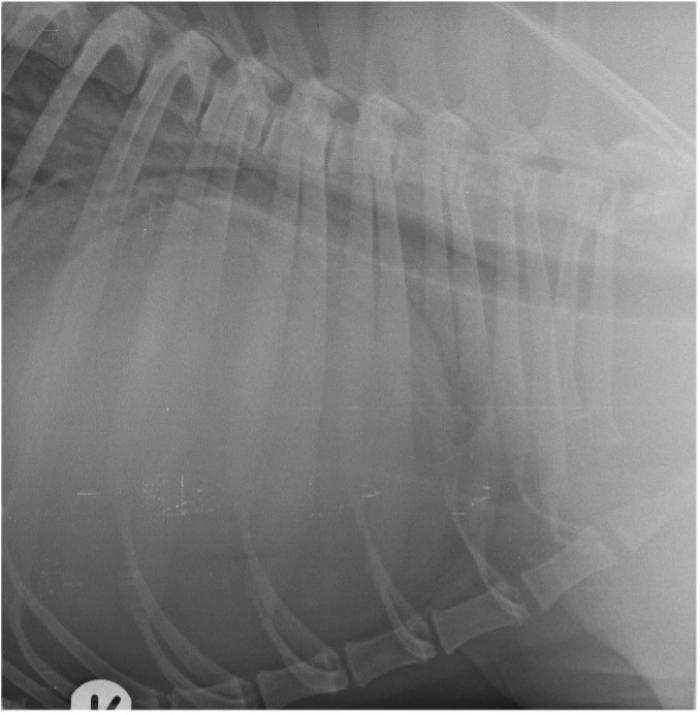

Se obtienen imágenes radiológicas del tórax en proyección laterolateral izquierda y derecha tras sedación ligera con butorfanol/midazolam vía endovenosa. En ambas proyecciones se observa una importante cardiomegalia generalizada, con un índice cardiaco vertebral igual a 16 (10.22 ± 0.20). Además, se aprecia una marcada elevación traqueal y compresión de la carina traqueal acompañado de elevación traqueal (Figura 1A-B). Estos hallazgos son compatibles con cardiomegalia o presencia de derrame pericárdico.

Figura 1. Radiografías de tórax del paciente en su proyección (A) laterolateral izquierda y (B) derecha, en las que se aprecia evidencia cardiomegalia.